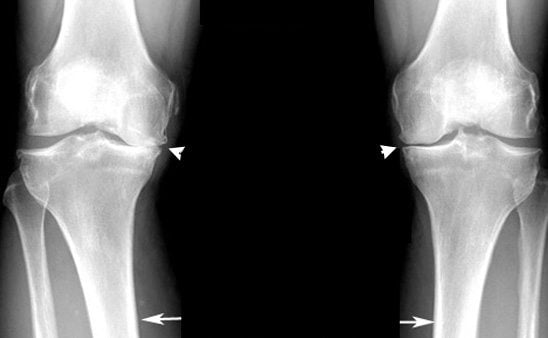

В ортопедии и травматологии остеоартроз классифицируют в зависимости от степени изменения хрящевых и костных структур, определяемой с помощью рентгенографии. Для каждой из них характерна своя клиническая картина.

| Вторая | На рентгеновских снимках хорошо заметны признаки разрушения хрящевой прослойки. На краях костных пластинок обнаруживаются множественные остеофиты. Болезненность усиливается, ощущается в ночные и дневные часы |

Методы диагностики

- рентгенография;